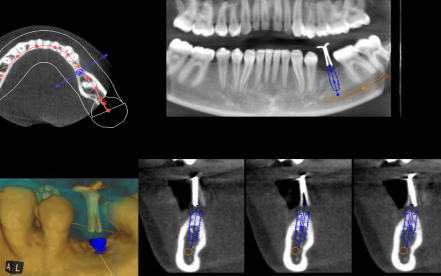

Die 3D-Röntgentechnik oder digitale Volumentomographie liefert 3-dimensionale Ansichten der Kiefer und der Zähne und ist ein großer Gewinn für die zahnärztliche Diagnostik. Bestimmte krankhafte Prozesse werden nur mit diesem Verfahren dargestellt. Häufig werden auch bisher versteckte Befunde entdeckt. Implantatplanungen können mit 3D-Röntgenaufnahmen präziser und vor allem sicherer vorgenommen werden. Exakte Vermessungen sind in diesen Ansichten möglich. Wurzelbehandlung (Endodontie) lassen sich sicher durchführen. Die 3D-Technik ermöglicht ein exaktes Erkennen der Wurzelanatomie, Lokalisieren und Vermessen der Wurzelkanäle. Parodontalbehandlungen (regenerative Parodontologie) lassen sich im Voraus planen. Dadurch kann die Behandlung gezielt und schonend durchgeführt werden. Weitere diagnostische Anwendungsgebiete der digitalen Volumentomographie liegen im Bereich der zahnärztlichen Chirurgie, z.B. für schwierige Weisheitszahnentfernungen, Lagebestimmungen von verlagerten Zähnen und Fremdkörpern.

Die 3D-Röntgentechnik oder digitale Volumentomographie liefert 3- dimensionale Ansichten der Kiefer und der Zähne und ist ein großer Gewinn für die zahnärztliche Diagnostik. Bestimmte krankhafte Prozesse werden nur mit diesem Verfahren dargestellt. Häufig werden auch bisher versteckte Befunde entdeckt. Implantatplanungen können mit 3D-Röntgenaufnahmen präziser und vor allem sicherer vorgenommen werden. Exakte Vermessungen sind in diesen Ansichten möglich. Wurzelbehandlung (Endodontie) lassen sich sicher durchführen. Die 3D- Technik ermöglicht ein exaktes Erkennen der Wurzelanatomie, Lokalisieren und Vermessen der Wurzelkanäle. Parodontalbehandlungen (regenerative Parodontologie) lassen sich im Voraus planen. Dadurch kann die Behandlung gezielt und schonend durchgeführt werden. Weitere diagnostische Anwendungsgebiete der digitalen Volumentomographie liegen im Bereich der zahnärztlichen Chirurgie, z.B. für schwierige Weisheitszahnentfernungen, Lagebestimmungen von verlagerten Zähnen und Fremdkörpern.